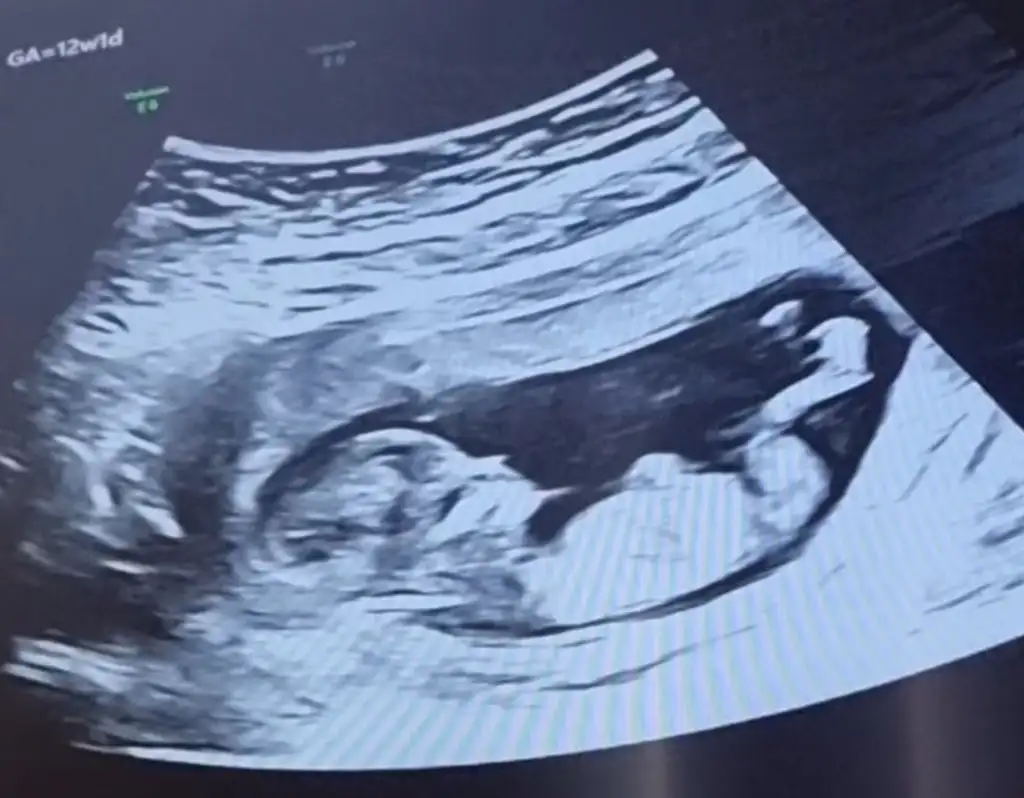

Daha küçük canım şimdilik erkek yönünde ama en iyi 11 12 13 haftalar olmalı9+1 karından usg bir tahmininiz olurmu bizim içinde![]()

Üstte çizdim orası bacak gibi görünmedi okla gösterdiğim yer nub gibiAnladım sanırım o dqer bacaqının qörüntüsü 3 hafta sonra kesin belli olacaqını düşünüoruz 16 haftalık olucak ozman söylerim cinsiyetni inş nasipse

Tekrar USG paylaşın demiştiniz 12+5 günlük burada doktor bir tahmin yapmadı ne düşünüyorsunuz :)Ikra meyra